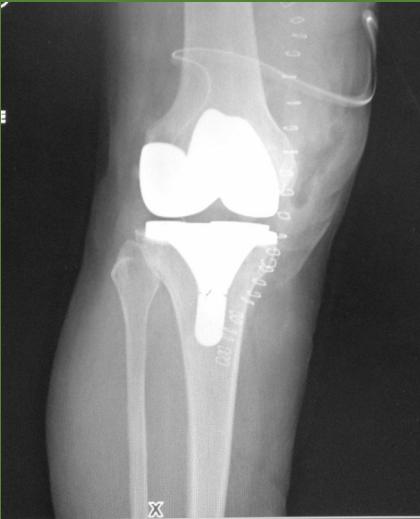

- ✓ Prosthetic joint

- Two weeks before planned Arthroplasty